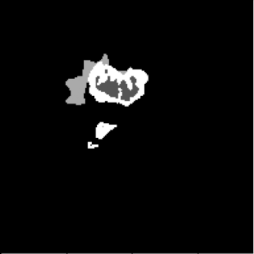

Diffusion with U-shape (Figure 5, PDF page 8)

Diffusion ground-truth mask.

Ground Truth

Diffusion prediction mask.

Prediction

DICE 69.44% · Best qualitative and quantitative segmentation quality.